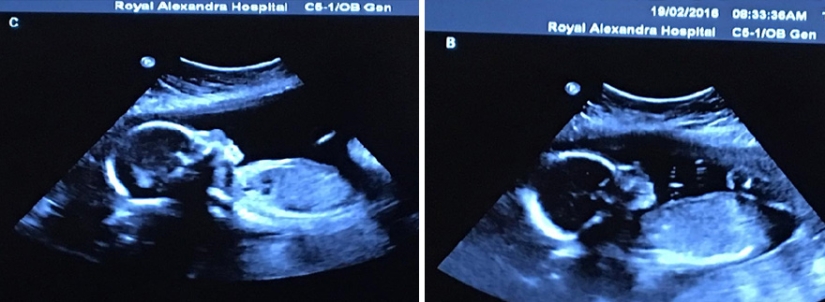

By Pictolic https://mail.pictolic.com/article/photo-shoot-of-very-rare-and-absolutely-identical-quadruplets.htmlThe chance of having four children (not with the help of IVF) is one in 729 thousand. And as you can imagine, the chance of having four identical twins is even less. But one Canadian couple was lucky. Bethany and Tim Webb, we can say, did almost the impossible — in May of this year they had four lovely and absolutely identical daughters — Abigail, McKayla, Grace and Emily. And this happens in one case out of 15 million!